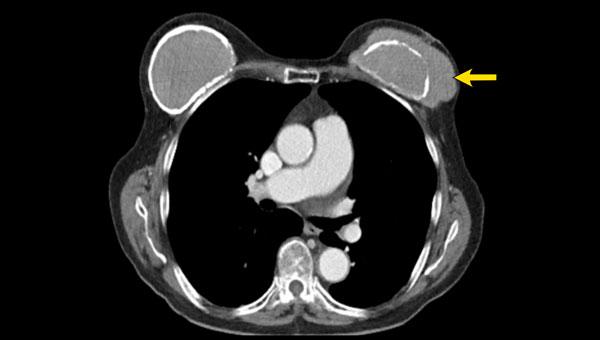

X-Quang và CT

X-Quang ngực và CT không đóng vai trò trong việc khảo sát túi ngực nhân tạo.

Đôi khi chúng có thể được phát hiện trên X-Quang, chẳng hạn khi có vôi hóa bao xơ hoặc khi nhìn thấy van bơm của túi giãn nở (mũi tên).

Phim ngực thẳng cho thấy vôi hóa bao xơ trong một túi ngực nhân tạo bị di lệch vào trong, không song song với đường viền tuyến vú.

CT của cùng bệnh nhân này cũng cho thấy vôi hóa ở mặt sau không đi theo đường viền của túi ngực, gợi ý vỡ túi trong bao xơ (mũi tên).

Một túi ngực còn nguyên vẹn có tỷ trọng bên trong đồng nhất màu xám trên CT, với lớp vỏ bao và bao xơ mỏng bao quanh có tỷ trọng cao hơn một chút.

Các bất thường về vị trí và các loại van bơm khác nhau đôi khi có thể được nhận thấy.

Bệnh nhân này có túi ngực bơm nước muối sinh lý với tỷ trọng bên trong thấp.

Quan sát thấy lớp vỏ bao mỏng, đều đặn, tỷ trọng cao hơn một chút.

Trên CT có thể thấy các loại van bơm khác nhau của túi ngực nhân tạo.

Vôi hóa bao xơ thường gặp và đôi khi có thể thấy dấu hiệu Linguine (mũi tên).